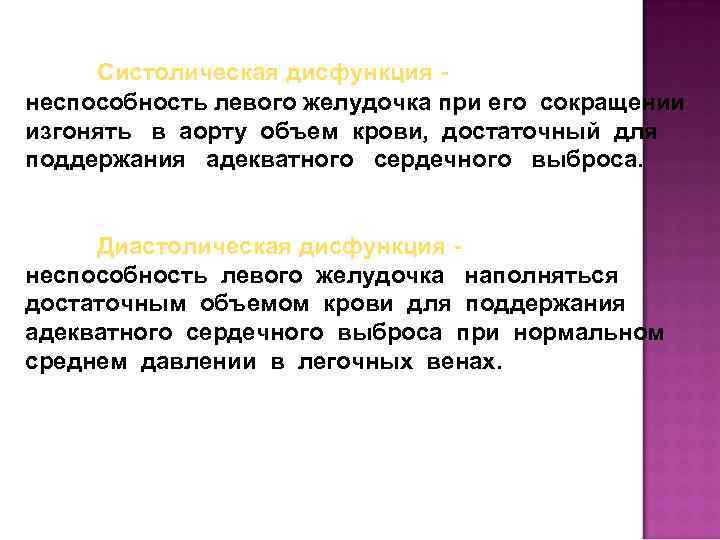

Систолическая дисфункция неспособность левого желудочка при его сокращении изгонять в аорту объем крови, достаточный для поддержания адекватного сердечного выброса. Диастолическая дисфункция неспособность левого желудочка наполняться достаточным объемом крови для поддержания адекватного сердечного выброса при нормальном среднем давлении в легочных венах.

Систолическая дисфункция неспособность левого желудочка при его сокращении изгонять в аорту объем крови, достаточный для поддержания адекватного сердечного выброса. Диастолическая дисфункция неспособность левого желудочка наполняться достаточным объемом крови для поддержания адекватного сердечного выброса при нормальном среднем давлении в легочных венах.